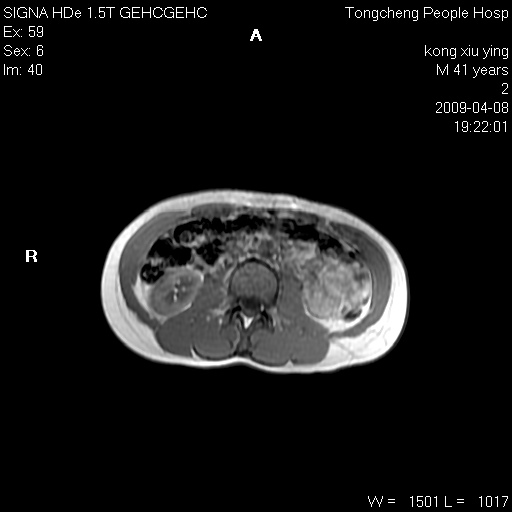

标题: CL1008:【经典】胆囊石榴籽样结石。 [打印本页]

标题: CL1008:【经典】胆囊石榴籽样结石。

女,41岁。健康体检——彩超提示:胆囊显示不清。平素健康,无不适感。

腹部mr扫描及mrcp,图像如下: